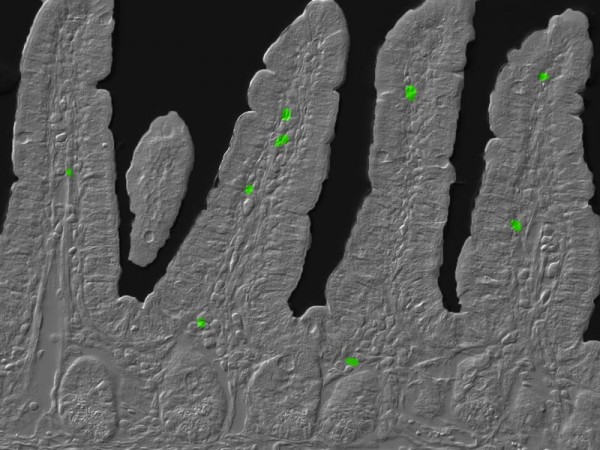

时间就是一切当生物钟被打乱,原本肠道中对抗感染的TH17细胞(图中绿色部分)会引起疾病。图片来源:Xiaofei Yu, Shipra Vaishnava and Yuhao Wang。

这种细胞是免疫细胞T细胞的一种,因表达白细胞介素17(Interleukin 17)而得名。这种物质能使其他T细胞提高免疫反应。在数量正常的情况下,生活在肠道中的TH17细胞能帮助身体对抗细菌和真菌的感染。但如果数量太多的话,这种免疫防御细胞就不再防病,反而开始致病。研究者们发现,提高培养的T细胞内的NFIL3水平,能减少转变为TH17的T细胞数量,这说明这种蛋白质的工作是防止T细胞朝那个方向特化。团队得出结论,这种蛋白质的缺失会造成TH17细胞活动的失控。